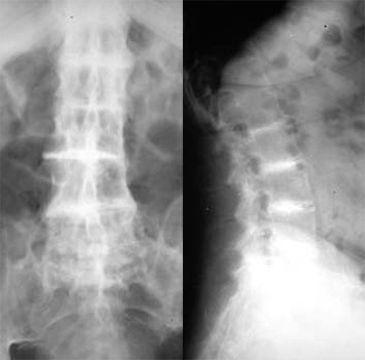

第三: 黑色尿、皮肤典型的色素沉着及脊椎、肩和膝等大关节特征性X线表现,构成褐黄病的三大特点,据此可做出诊断。有条件时可做血、尿的尿黑酸特殊检查。

第一:本病最严重的并发症是关节病变。与类风湿关节炎不同,本病主要侵犯脊柱和肩、髋等大关节,而骶髂及手、足小关节很少受累。男性病人发病早且较重,膝关节最常受累,并且损害程度也最重。脊柱病变也是本病最常见的骨关节损害,常表现为下背部僵硬和疼痛,病变最早发生于腰椎,随着病情的发展,可波及胸椎,使脊柱运动受阻,脊柱生理弯曲消失。椎间盘突出和钙化也是本病特征性表现,典型病人呈前倾鸭子步态。病变膝关节受轻度外伤后,可引起关节腔积液,滑膜液为非炎症性,主要含有单核细胞。关节镜检可见滑膜黑染。关节腔积液消失后可逐渐发生关节挛缩。